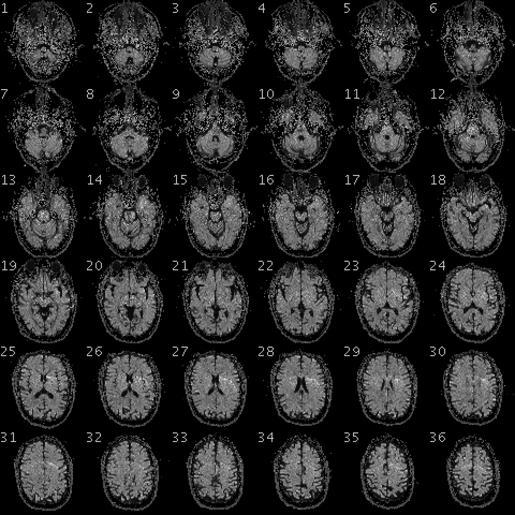

MAKE A MEME View Large Image 100325 RS88UH 11 qc.gif en fMRI of the brain/head of a PGP participant with the following data Demographic Information Date of Birth 1954-08-28 58 years old Gender Male Weight 246lbs 112kg Height 6ft 5in 195cm Blood Type O+ Race White https ...

View Original:100325 RS88UH 11 qc.gif (480x480)

Keywords: 100325 RS88UH 11 qc.gif en fMRI of the brain/head of a PGP participant with the following data Demographic Information Date of Birth 1954-08-28 58 years old Gender Male Weight 246lbs 112kg Height 6ft 5in 195cm Blood Type O+ Race White https //my personalgenomes org/profile/hu43860C Personal Genome Project https //my personalgenomes org/profile/hu43860C PGP Scientists 2010-04-29 cc-zero To the extent possible under law PersonalGenomes org has waived all copyright and related or neighboring rights to Personal Genome Project Participant Genetic and Trait Dataset This work is published from United States Magnetic resonance imaging Personal Genome Project